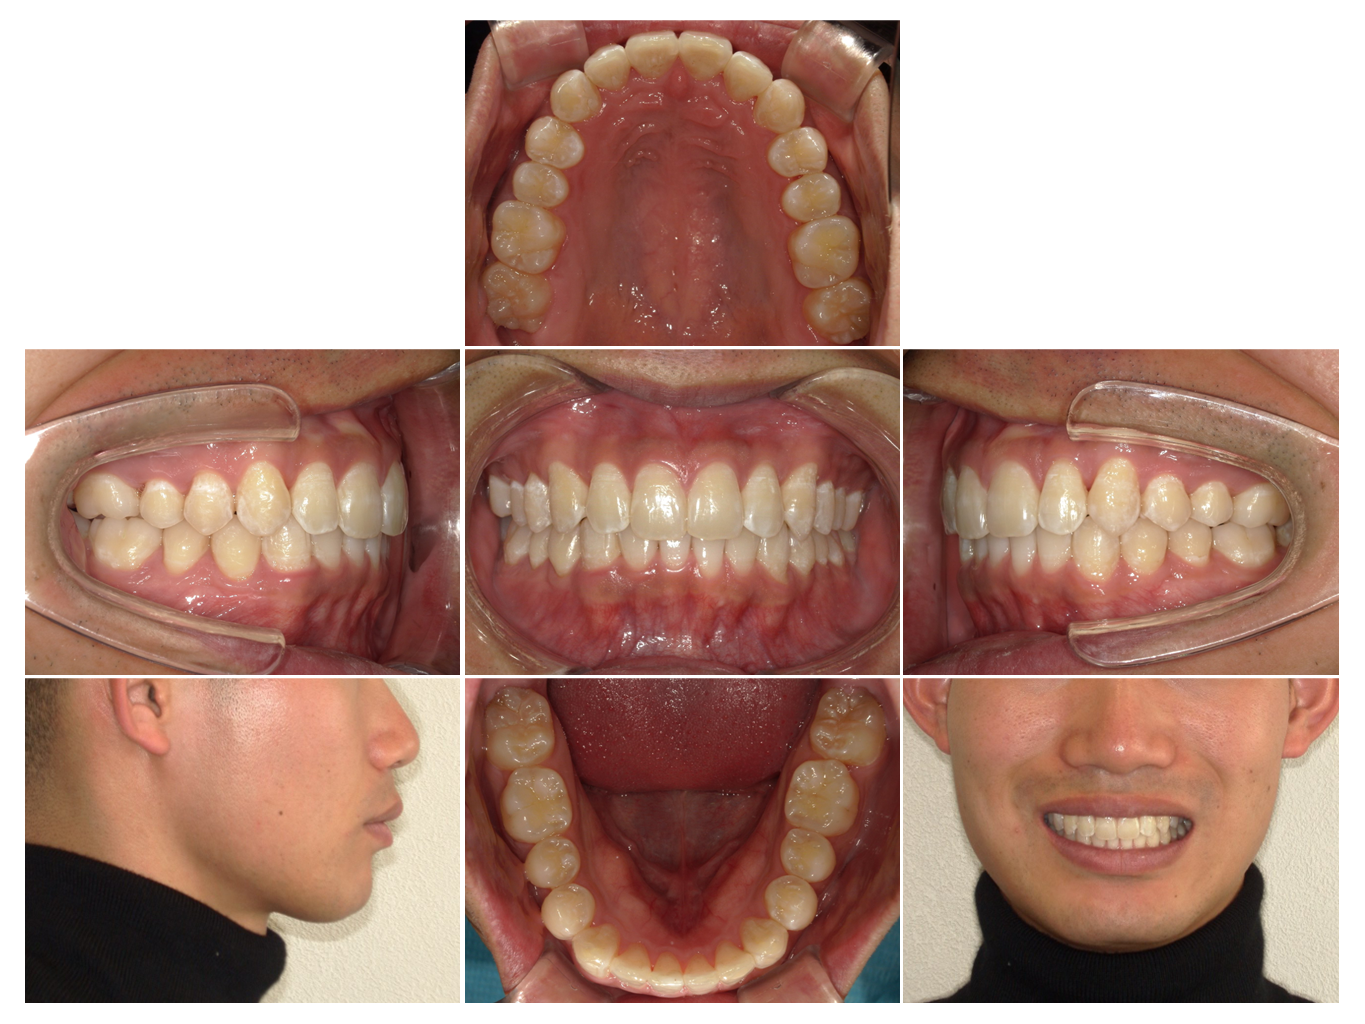

症例4

| 来院時の主訴 | 全体的なガタガタ |

| 医院での対応や適用装置 | マウスピース矯正装置を使用して主訴である |

| 通院期間 | 11ヶ月 |

| 通院回数 | 5回 |

| 治療費用総額 | 852,500円(税込) |

| リスクと副作用 | 矯正治療による歯の移動に伴う痛み、歯根吸収、虫歯 |